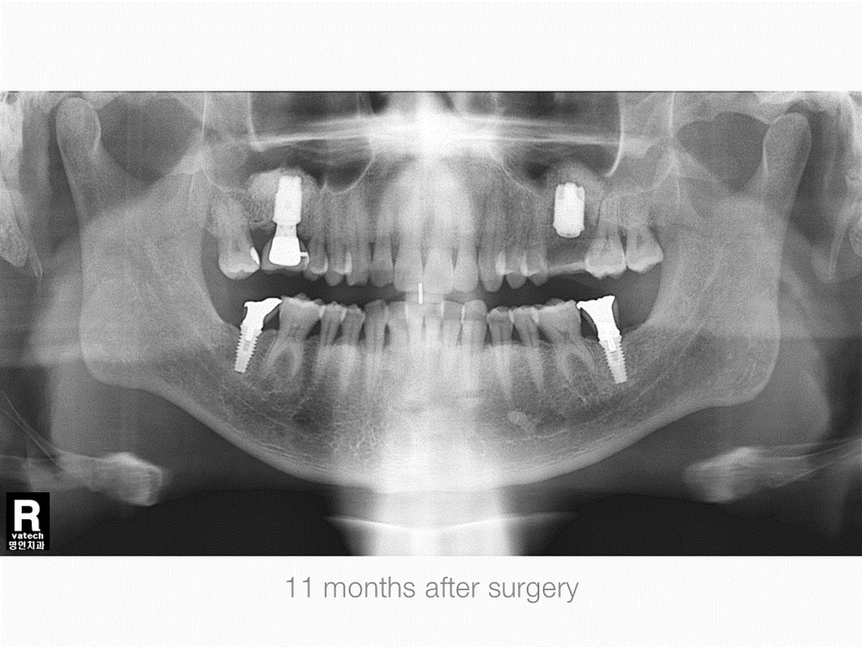

Right Maxillary, First Molar Area, Sinus & Crestal Augmentation

Gender: Male

Age: 53 years old

Operation Site: #16 Sinus Graft, Crestal Defect